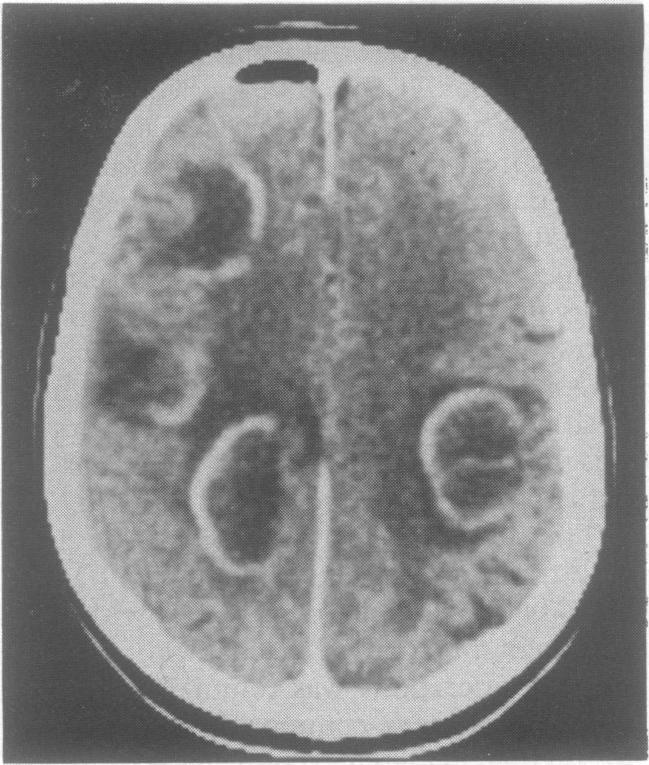

Atypical meningitis complicating a penetrating head injury.

J Neurol Neurosurg Psychiatry. 1991 Jan;54(1):92-3. doi: 10.1136/jnnp.54.1.92-a.

Atypical meningitis complicating a penetrating head injury.穿透性头部损伤并发非典型脑膜炎。